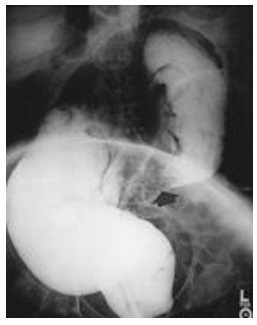

“Paciente J.A.B, masculino, 64 anos, deu entrada no Pronto Socorro com queixa de dor abdominal súbita há mais ou menos 6 horas, do tipo em cólicas em andar inferior do abdome, com distensão quase imediata. Associado, refere parada de eliminação de gases e fezes e dois episódios de vômitos com conteúdo alimentar. Nega cirurgias prévias e quadros semelhantes anteriormente. Ao exame físico apresentava-se em bom estado geral, a não ser fácies de dor, gemente, corado, levemente desidratado, frequência cardíaca de 118 batimentos por minuto e abdome globoso, distendido com ruídos hidroaéreos diminuídos, doloroso à palpação difusamente com mais intensidade em baixo ventre e hipertimpânico à percussão. Realizou radiografia simples de abdome, tomografia de abdome e radiografia de clister opaco demonstrados abaixo respectivamente”.